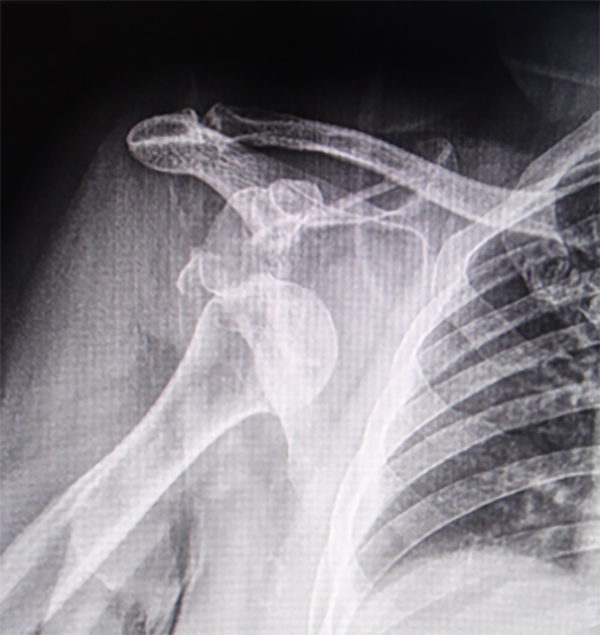

Presentamos el caso de una paciente de sexo femenino de cincuenta y cuatro años que sufrió un accidente de tránsito en diciembre del 2020, en el momento, acudió a emergencias en otro centro de salud con dolor y deformidad de hombro derecho (dominante). En la radiografía AP se evidencia luxación glenohumeral anteroinferior (fig. 1).

Figura 1: Radiografía AP (no verdadera) de hombro se comprueba luxación glenohumeral anteroinferior.